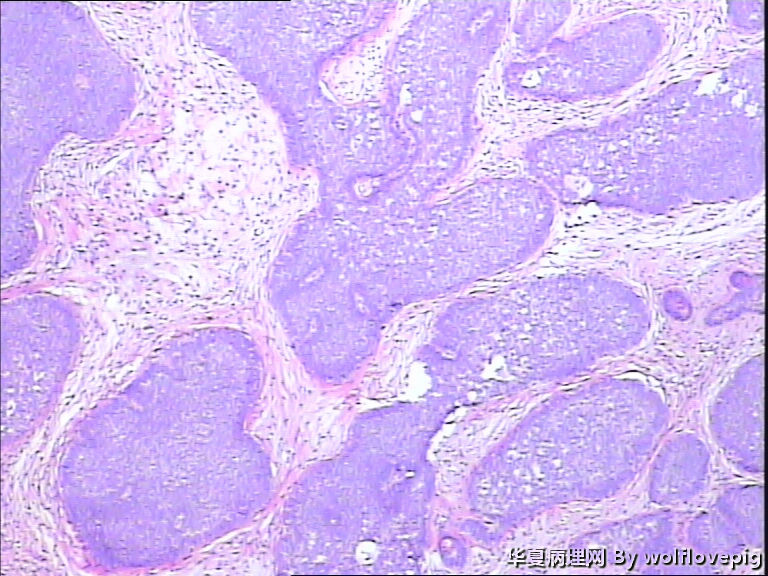

女,58y,右面部包块10年。灰白不整形带皮组织一块:2.3cm*1.5cm*0.3cm,切面有一灰白区域,质软,边界欠清。

诊断考虑毛母细胞瘤,或毛发上皮瘤。

基底细胞癌

毛母细胞瘤

毛发上皮瘤

没有基底样物质,没有收缩裂隙,细胞异型不大,无明确核分裂像,考虑:附属器肿瘤,有点像汗腺来源的,如真皮导管瘤或螺旋瘤。请老师指点。

栅栏状外周结构,疏松的间质,基底细胞癌

与表皮无关,表皮无破溃,无收缩间隙-------不支持BCC  有角囊肿 促纤维增生-----支持毛发上皮瘤